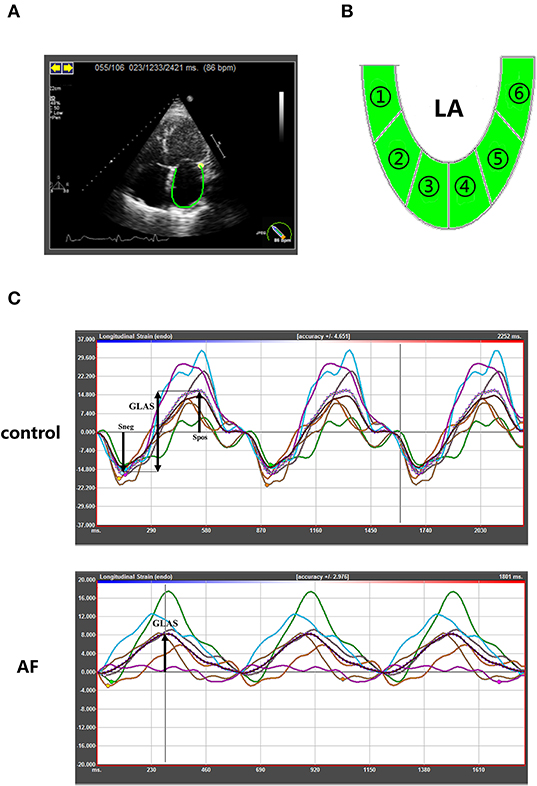

In order to assess the LA performance with or without AF at different ages, all participants underwent echocardiography examination before ablation. The procedure was conducted as described in our previous study (17). The measurements of two-dimensional and tissue Doppler echocardiographic parameters, including LA dimension (LAD), left ventricular end-diastolic dimension (LVEDD), left ventricular end-diastolic posterior wall thickness, left ventricular septal wall thickness, left ventricular ejection fraction (LVEF), pulmonary artery dimension (PAD), E peak velocity and A peak velocity, were carried out using commercially available iE33 instruments (Philips Medical Systems, Koninklijke, the Netherlands) according to the guideline of the American Society of Echocardiography and the European Association of Cardiovascular Imaging (18–20). Left ventricular mass (LVM) index is calculated according to Devereux formula [LVM index = (LVM)/body surface area]. The measurement of LVM is according to the recommendations (18). Then two-dimensional speckle tracking echocardiography was performed offline by analysis of gray-scale images (four-chamber views) using commercially available software (TomTec Imaging Systems GmbH, Unterschleissheim, Germany). LA endocardial borders were manually traced in four-chamber and two-chamber views (Figure 1A), and LA was divided into six segments subsequently (Figure 1B). The software then generated longitudinal deformation curves and measured the mean values of strain and strain rates. Average of at least three beats was taken in per measurement process. LA strain rates (SRa, SRe, and SRs) and LA global longitudinal strain were analyzed to evaluate LA performance. The LA global longitudinal strain (GLAS) was calculated as the value of longitudinal peak early-diastole strain (Spos, positive peak strain) minus longitudinal peak late-diastole strain (Sneg, negative peak strain). Because of impaired atrial contractility during AF rhythm, Sneg was close to 0. GLAS of AF patients was identified as the value of Spos (Figure 1C). On this basis, LA stiffness index based on strain imaging was defined as the ratio of E/e′ to GLAS [LA stiffness index = (E/e′ ratio)/GLAS] as demonstrated previously (21). All the procedures were performed by two fixed operators.

Figure 1. Speckle-tracking echocardiography to quantify LA strain in control and AF patients at three age groups. (A) Representative apical four-chamber view echocardiogram of a control adult. Along the inner contour of the LA wall, we define the target region. (B) The six segments of the LA wall were into strain analysis. (C) The strain curves of six segments and average strain curve (dotted line). The GLAS of control patients were defined Spos minus Sneg. In AF patients, GLAS was identified as the value of Spos. GLAS, left atrial global longitudinal strain; Spos, longitudinal peak early-diastole strain; Sneg, longitudinal peak late-diastole strain.